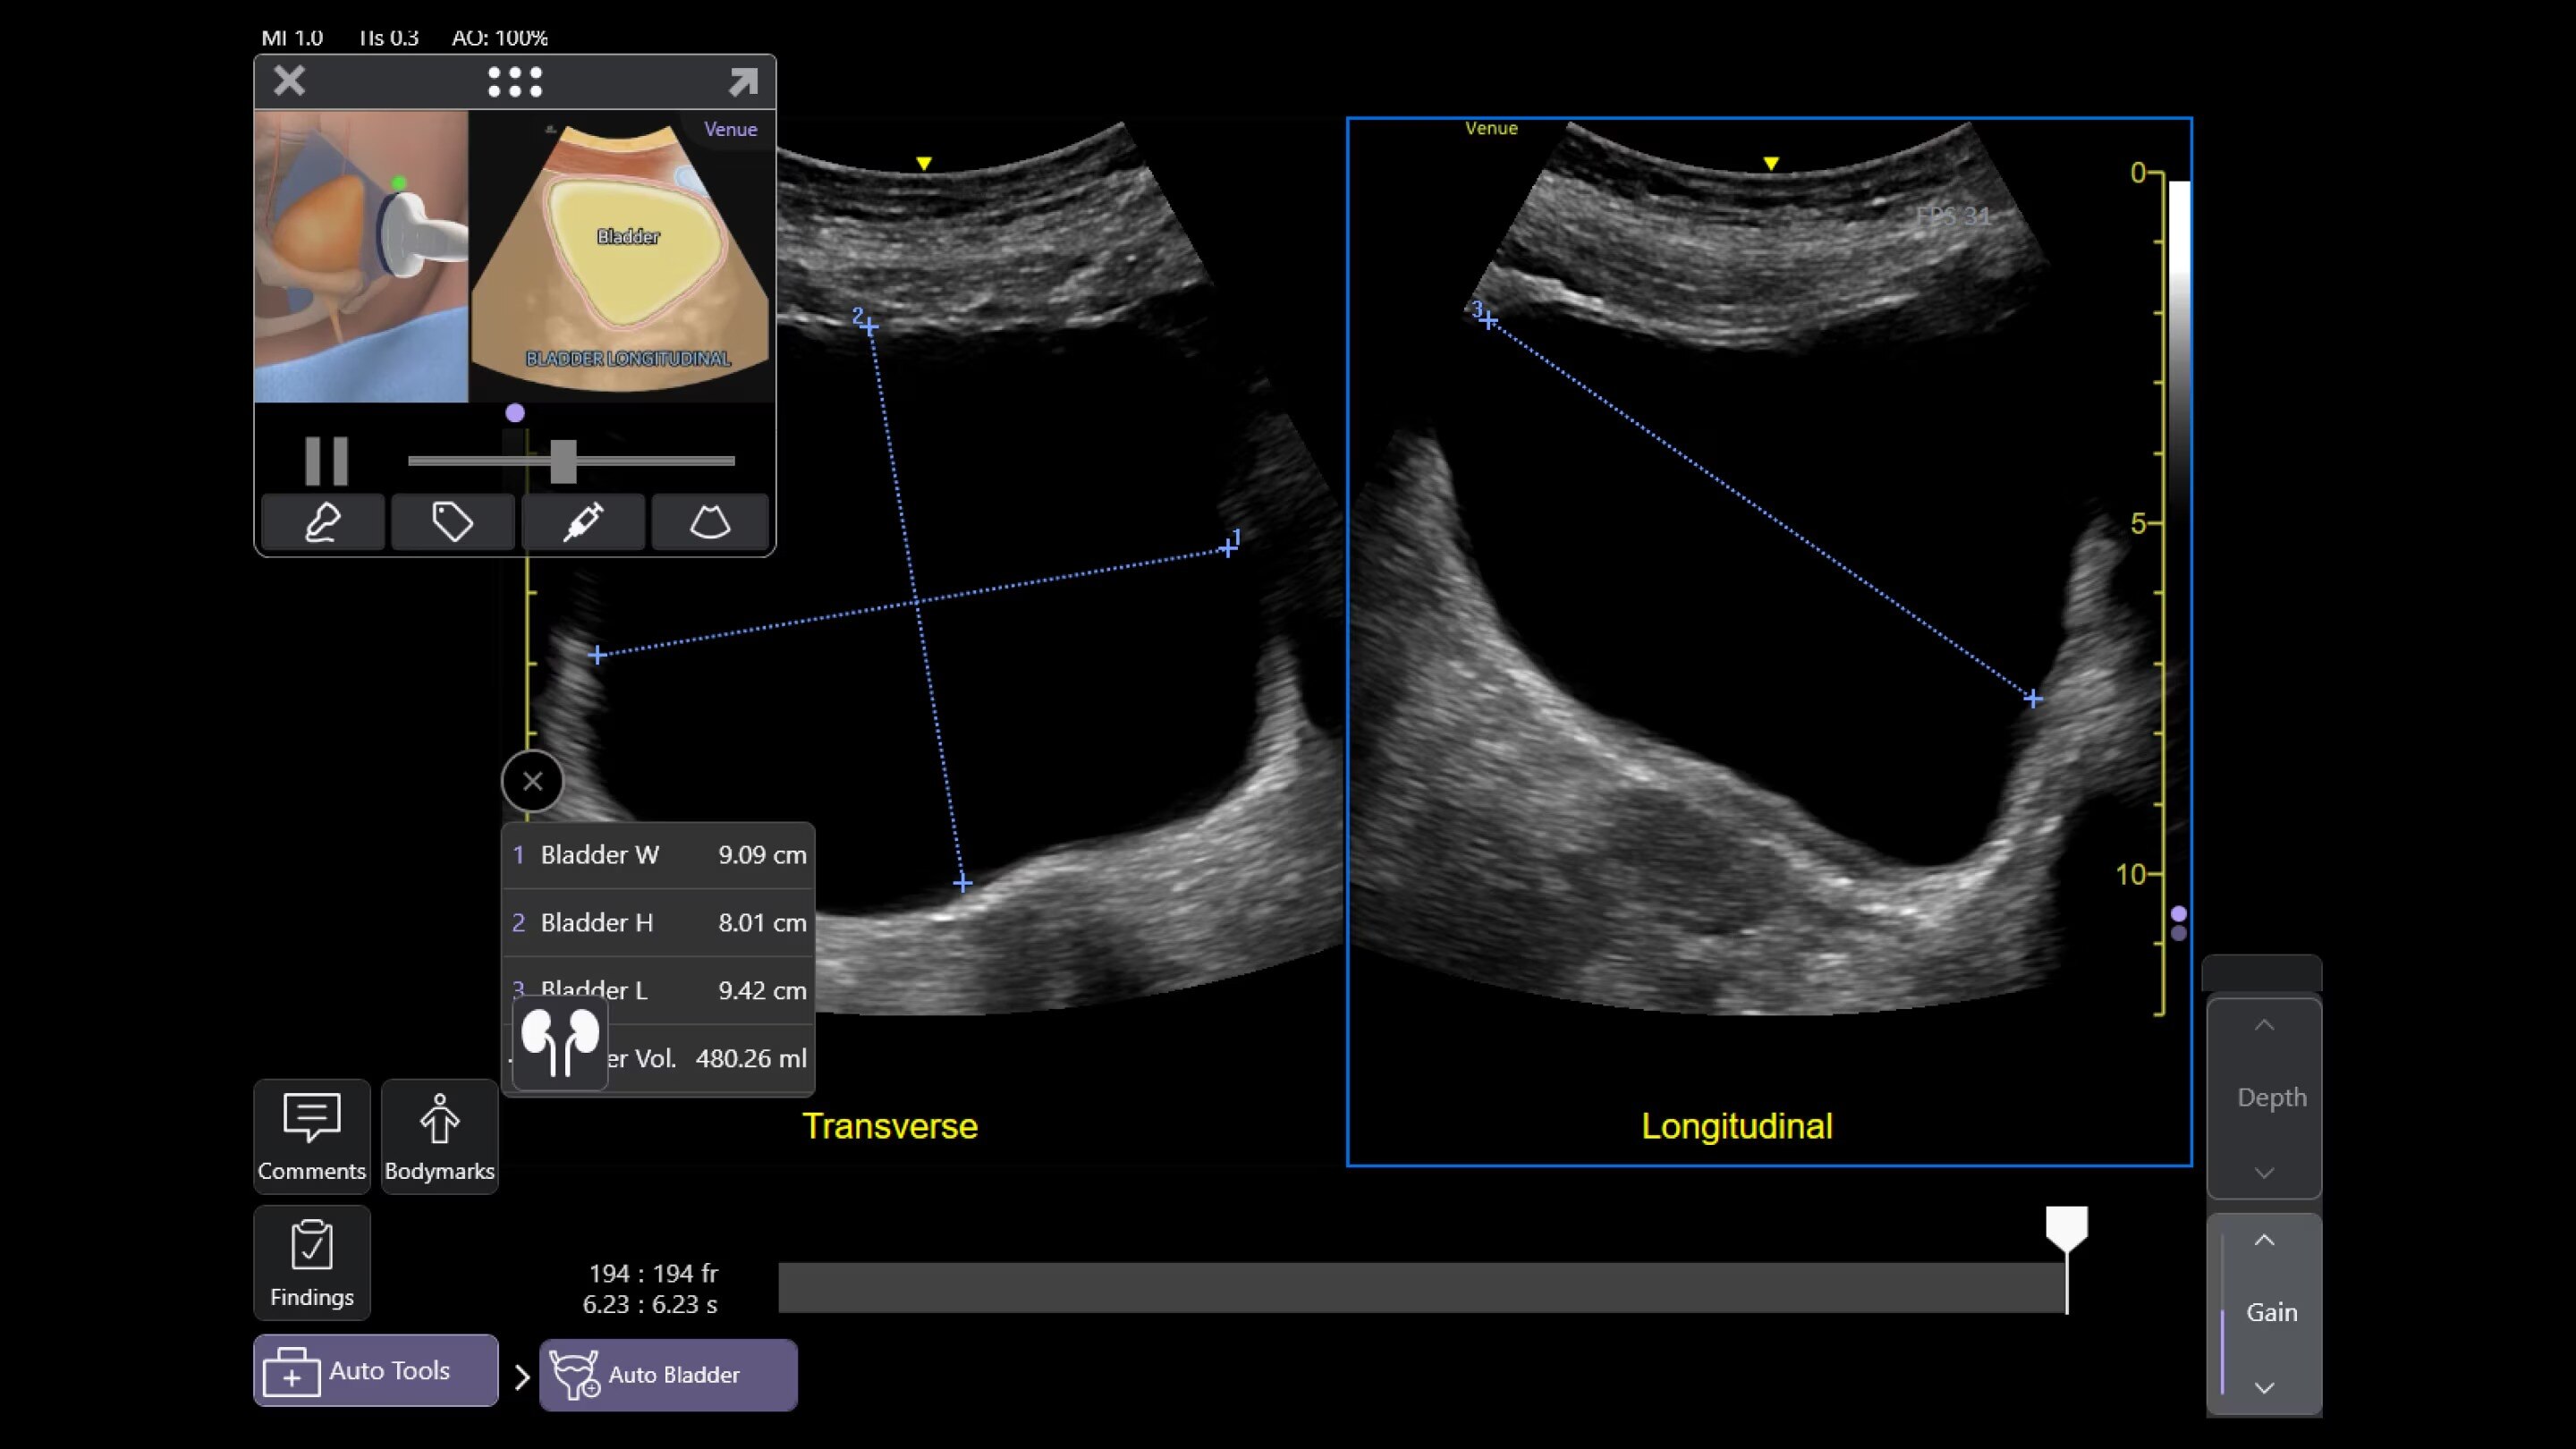

Auto Bladder Volume

Quick and easy measurements

AI-enabled tool provides rapid and easy urinary bladder volume measurements, saving clinicians valuable time and enhancing clinical accuracy. It measures bladder dimensions and calculates the bladder volume from two views: transverse and longitudinal.